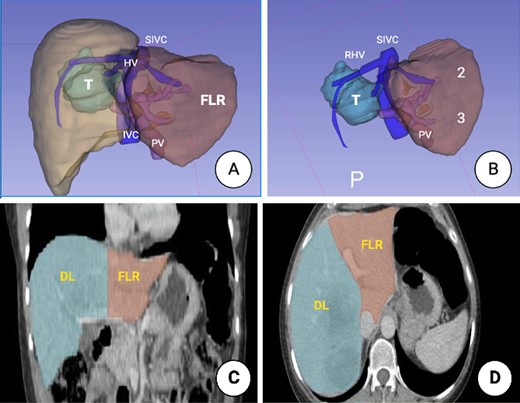

Prior to surgery, a 3D liver reconstruction image with liver volumetry was performed using a free open-source software (3D Slicer) (Fig. 2). Liver volumetry calculated the volume of the right lobe and segment 4 was 1401.2 cc (77% of the total volume) and the volume of segments 1, 2 and 3 was 418 cc (23% of the total volume), given the previous exposure to chemotherapy and an insufficient FLR with a future liver remanent/weight ratio (FLR/WR) of 0.44, it was decided to perform an extended right hepatectomy using the ALPPS technique (Fig. 3). It was calculated the Comprehensive ALPPS Preoperative Risk Assesment (CAPRA) score wich was of 3.96, with an estimated 90d mortality <7% and the pre-stage 1 ALPPS risk model of 0 points with an early mortality risk of 2.7%. The PO course was uneventful, until the PO Day 7, when the fluid drain turned milky, chylous ascites was confirmed by determination of triglyceride levels in the drainage fluid at 300 mg/dL; thus, management with medium chain fatty acids rich diet, parenteral nutrition and somatostatin analog (octreotide) was started. On PO Day 10 of treatment, there was evidence of decreased drainage volume and serous discoloration with a normalization of triglyceride fluid levels, so a normal diet was started with adequate tolerance, the liver function tests were normal at that time, and the patient was discharged on PO Day 11 (Fig. 4).

3D image reconstruction. (A) Right hemi-liver mass involving segments 5, 6, 7 and 8. The relation to the suprahepatic veins (HV), IVC and the PV is shown. (B) Future liver remnant (FLR) (Segments 2 and 3). SIVC, suprahepatic inferior vena cava; PV, portal vein; FLR, future liver remnant. (C) Liver volumetry. Coronal plane delimiting the transection line planned and the FLR. (D). Axial plane, showing the transection line planned and the FLR.